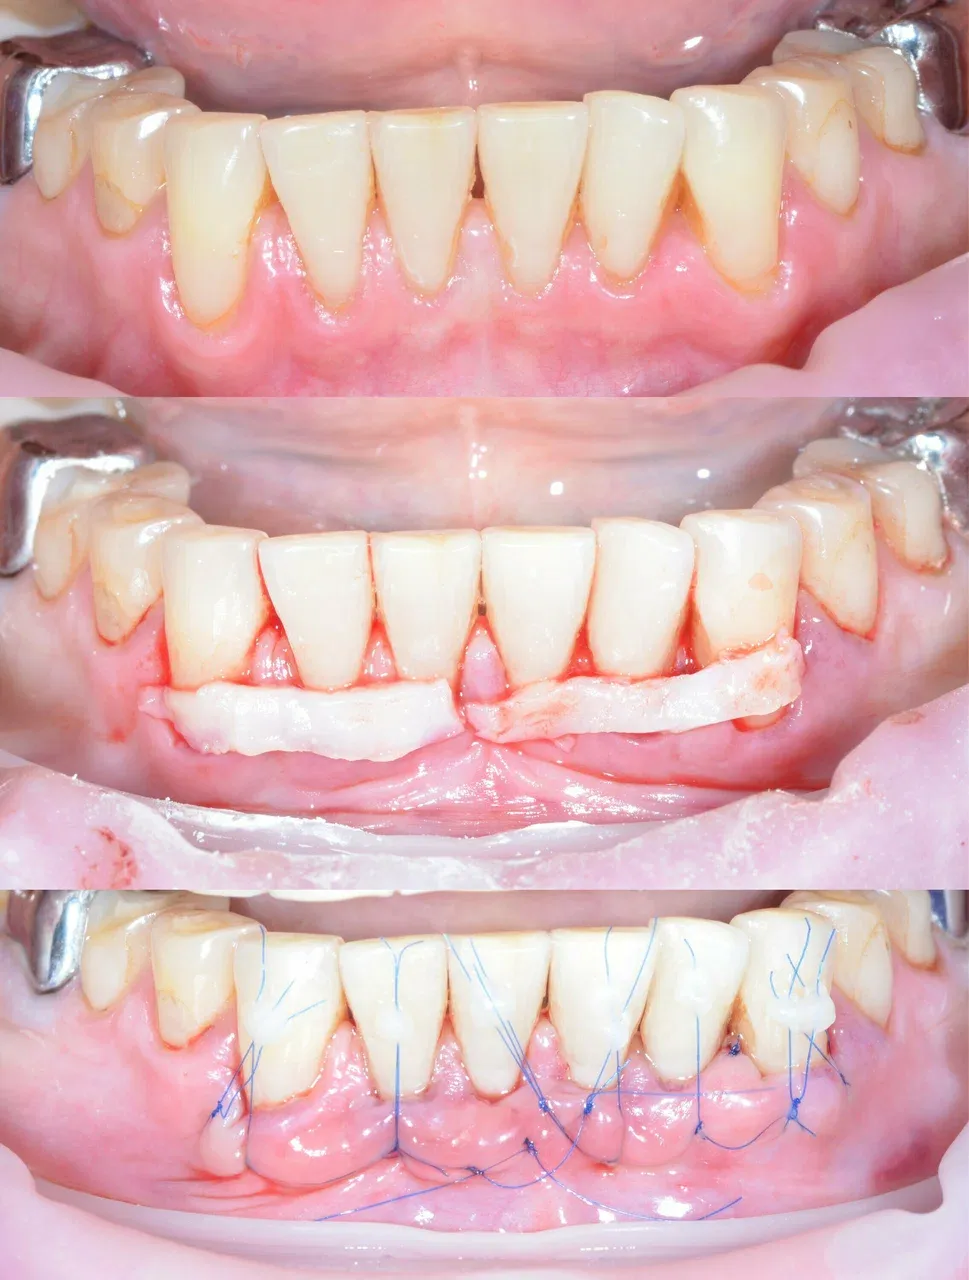

Имплантация зубов челюсти - фото до и после